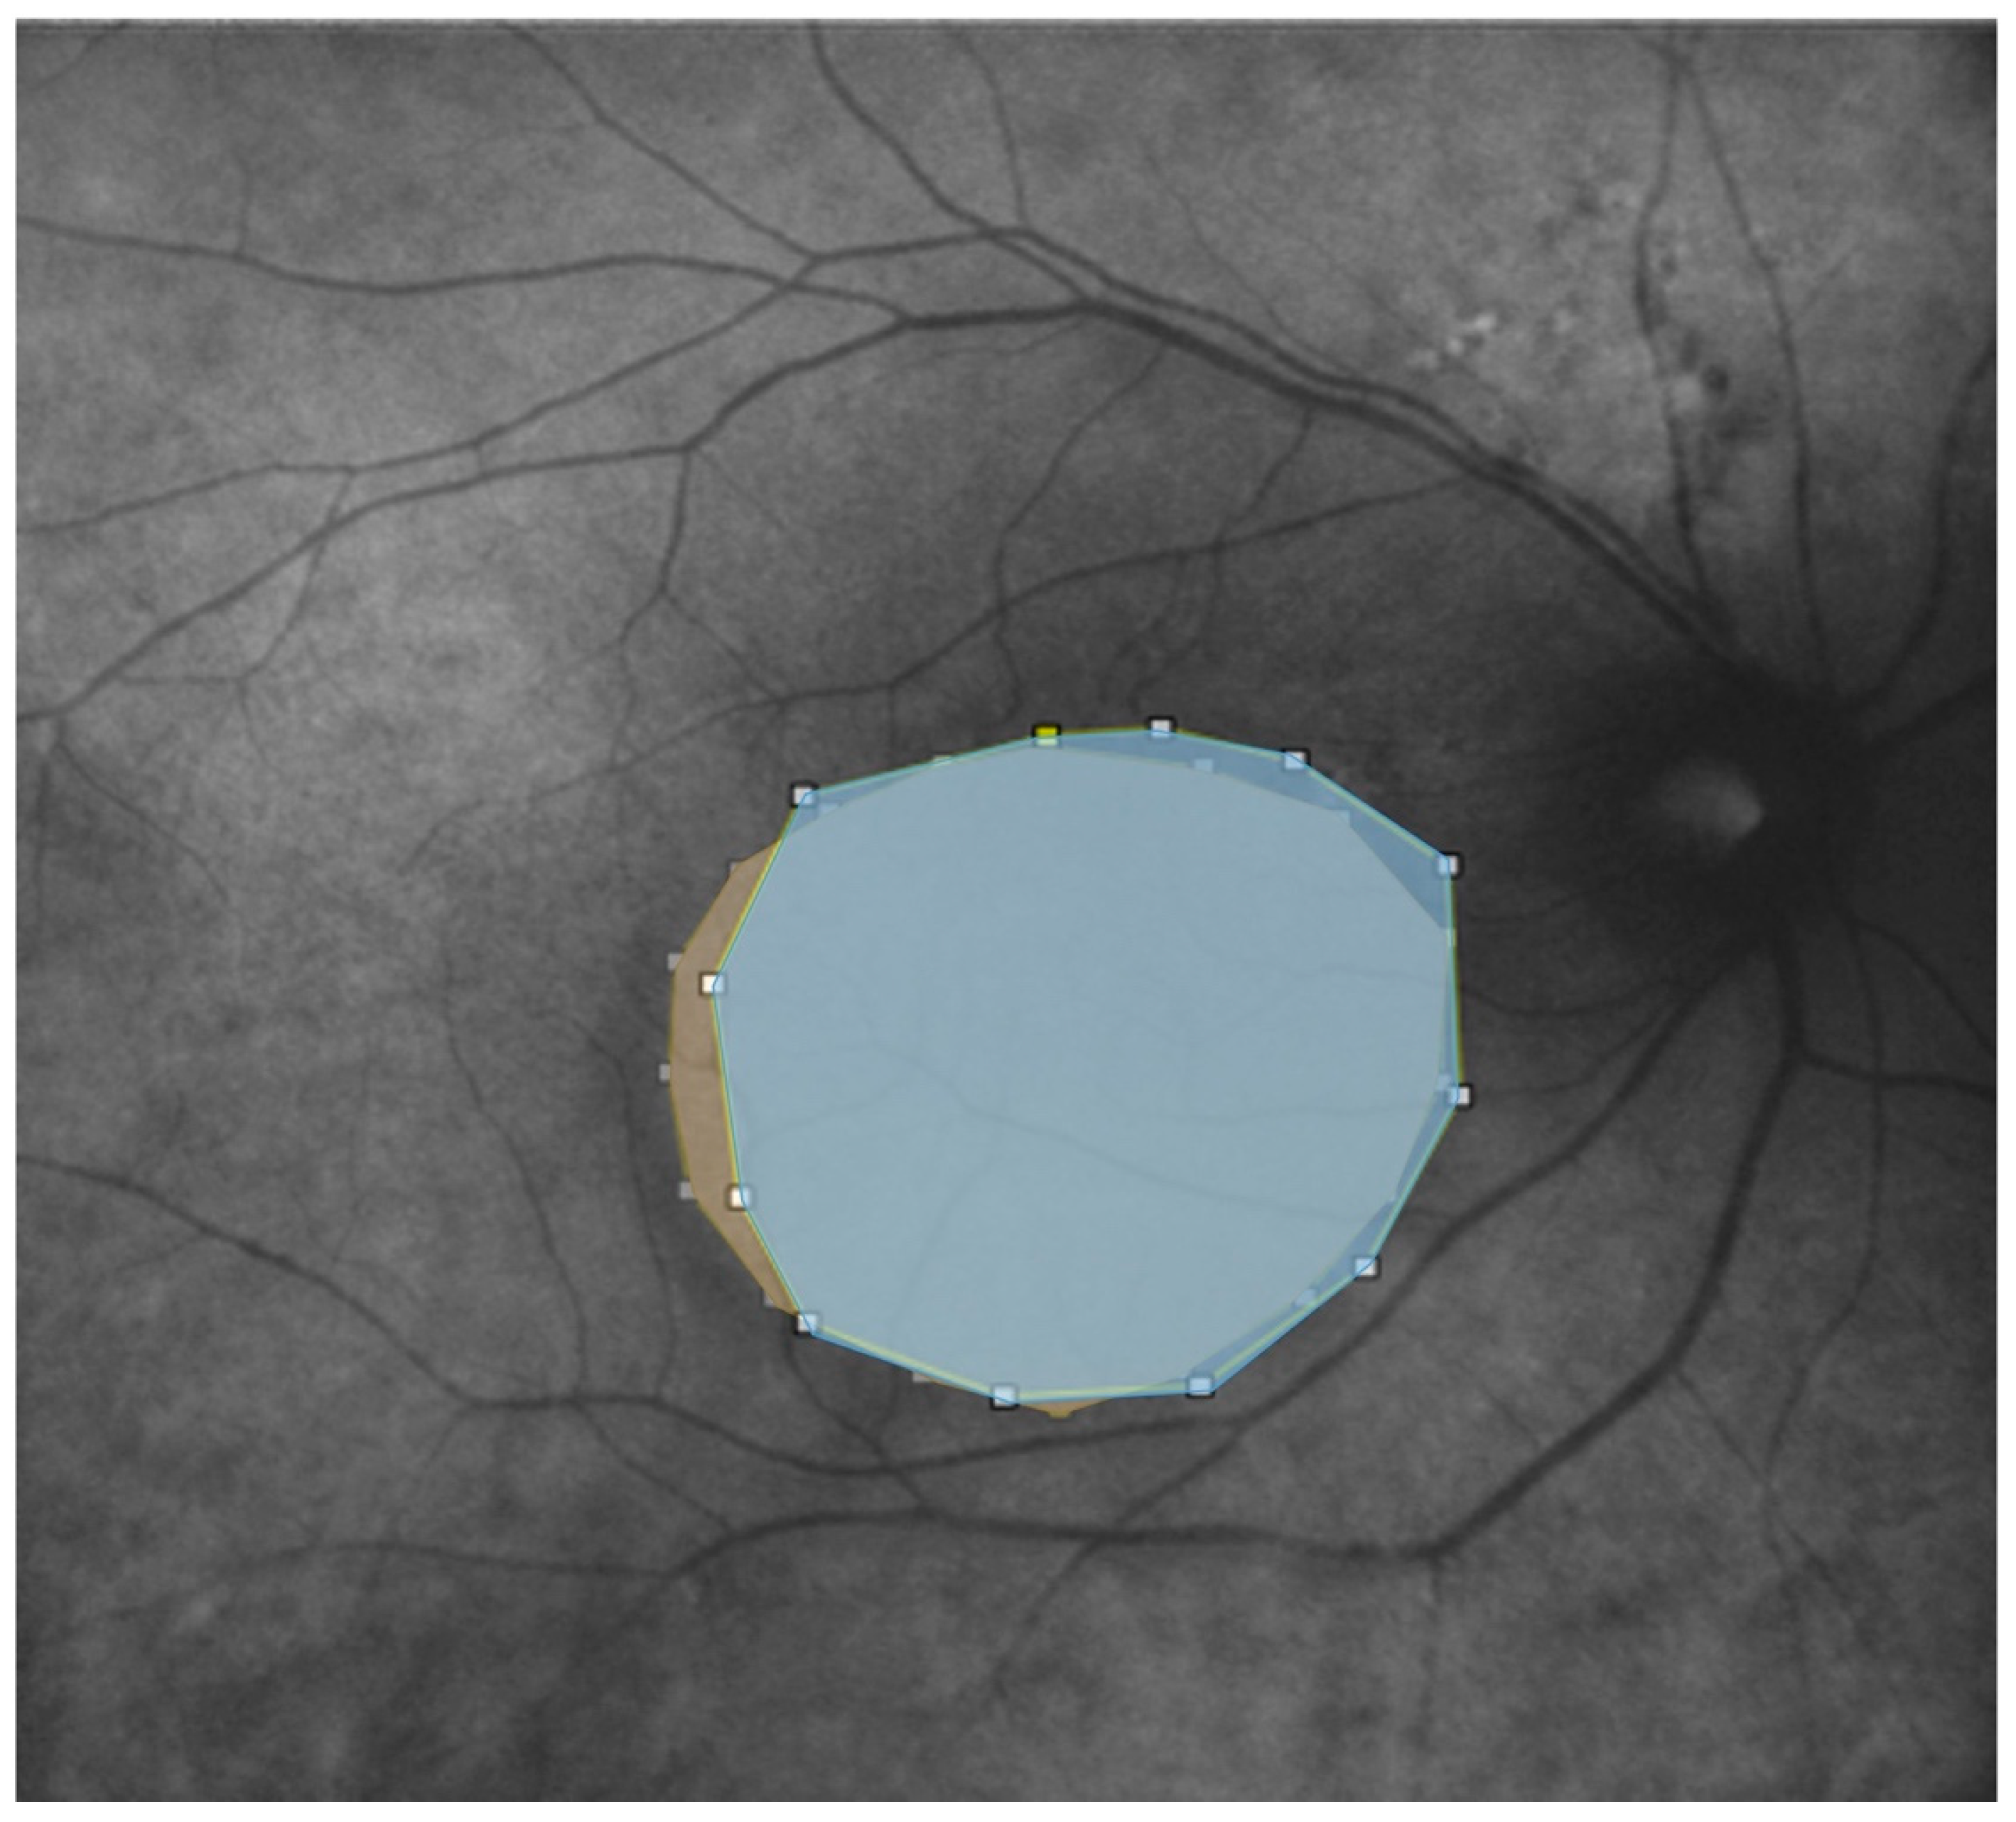

Figure 3.

Retromode imaging (A), autofluorescence (B) and enface (C) of the same patient shows serous neuroretinal detachment in the macular region; this was outlined using the provided caliper tool on ImageJ software (on the right).

We further evaluated the extent (area expressed in mm2) of the disease features in AF, RM, and enface scans using ImageJ 1.8.0_345 software (ImageJ 1.53 k, National Institutes of Health, Bethesda, MD, USA) (Figure 3 and Figure 4). First, each image was converted to 8 bits, and the scale was set according to the size of the scan in millimeters, which was then converted into pixels. Then, we manually outlined the region of interest (ROI) with the provided caliper tool, and the software provided the area of the ROI. The ROIs were manually selected by two co-authors. A retinal specialist checked the segmented regions once the images were collected. If all three operators agreed, the image was consequently included in the analysis. Cohen’s coefficient analysis was used to ensure a concordance of at least 0.90. A neuroepithelium serous detachment was identified on the enface images as a hyporeflective area; within the enface images, it usually appeared isoautofluorescent. The pseudo-3D effect of retromode imaging helped to outline the detached area. RPE atrophy appeared as hyper- or hypoautofluorescence on AF with hyperreflective areas on enface imaging and mottling on RM imaging.